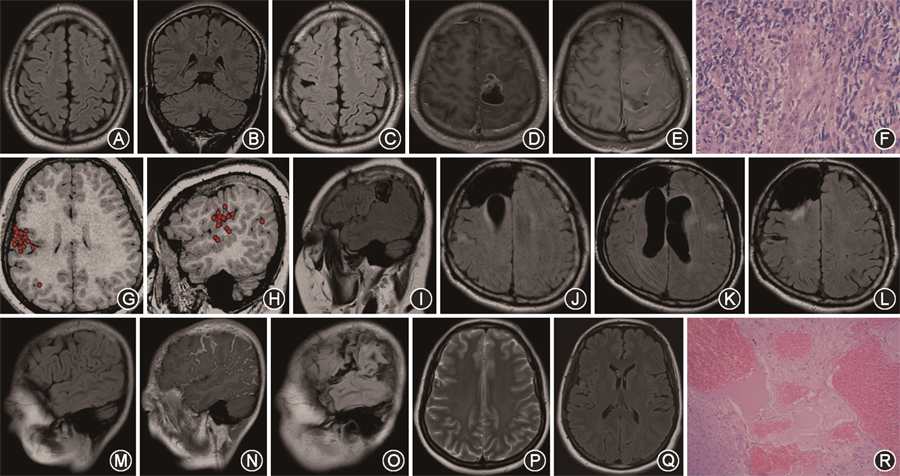

1.患者病因分析:53例患者中局灶性皮质发育不良患者15例(28.3%,图1A~C),病因不明确患者11例(20.8%),肿瘤10例(18.9%,图1D~F),头外伤5例(9.4%,图1G~I),结节性硬化4例(7.6%,图1J~L),脑面血管瘤病3例(5.7%,图1M~O),脑回畸形2例(3.8%),其他1例(1.9%,病理结果为纤维钙化伴固醇结晶),海绵状血管瘤1例(1.9%,图1P~R),孕期缺氧1例(1.9%)。